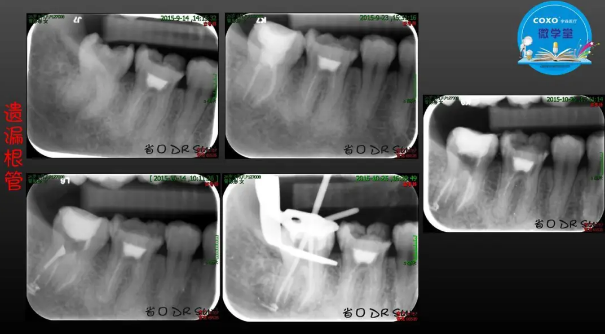

主講:孫書昱

主任醫(yī)師,牙體牙髓副主任, 廣東省口腔醫(yī)院牙體牙髓科 主任醫(yī)師。2003年碩士研究生畢業(yè),研究方向?yàn)檠荔w牙髓病學(xué),擅長(zhǎng)于牙體牙髓病的診斷、齲齒、牙髓炎、根尖周病的治療以及前牙美容修復(fù)。